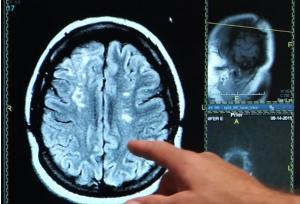

La fenêtre d'intervention est très courte, à la suite de l'AVC, rappellent les auteurs, « un laps de temps crucial pour recevoir les soins permettant de rétablir le flux sanguin et réduire ou inverser les dommages au cerveau ». Ce sondage montre que les patients plus jeunes, les adultes de moins de 45 ans, ont tendance à sous-estimer l'urgence des symptômes d'AVC au point de retarder leur prise en charge à l'hôpital. Le Dr David Liebeskind, professeur de neurologie, et auteur principal rappelle que plus le cerveau sera privé du flux sanguin ou envahit par l'hémorragie, plus dévastatrices seront les conséquences pour le patient.

L'AVC ischémique peut se produire à tout âge : La plupart des jeunes patients, environ 85% souffrent d'AVC ischémique, conséquence du manque d'apport d'oxygène dans une partie du cerveau lié à un blocage des artères. L'AVC ischémique est souvent associée à l'hypertension artérielle, au diabète, au tabagisme et à l'obésité. Mais les mesures de mode de vie, comme une alimentation équilibrée, la pratique régulière de l'exercice, l'absence de tabagisme et d'excès d'alcool, contribuent à réduire le risque d'AVC.